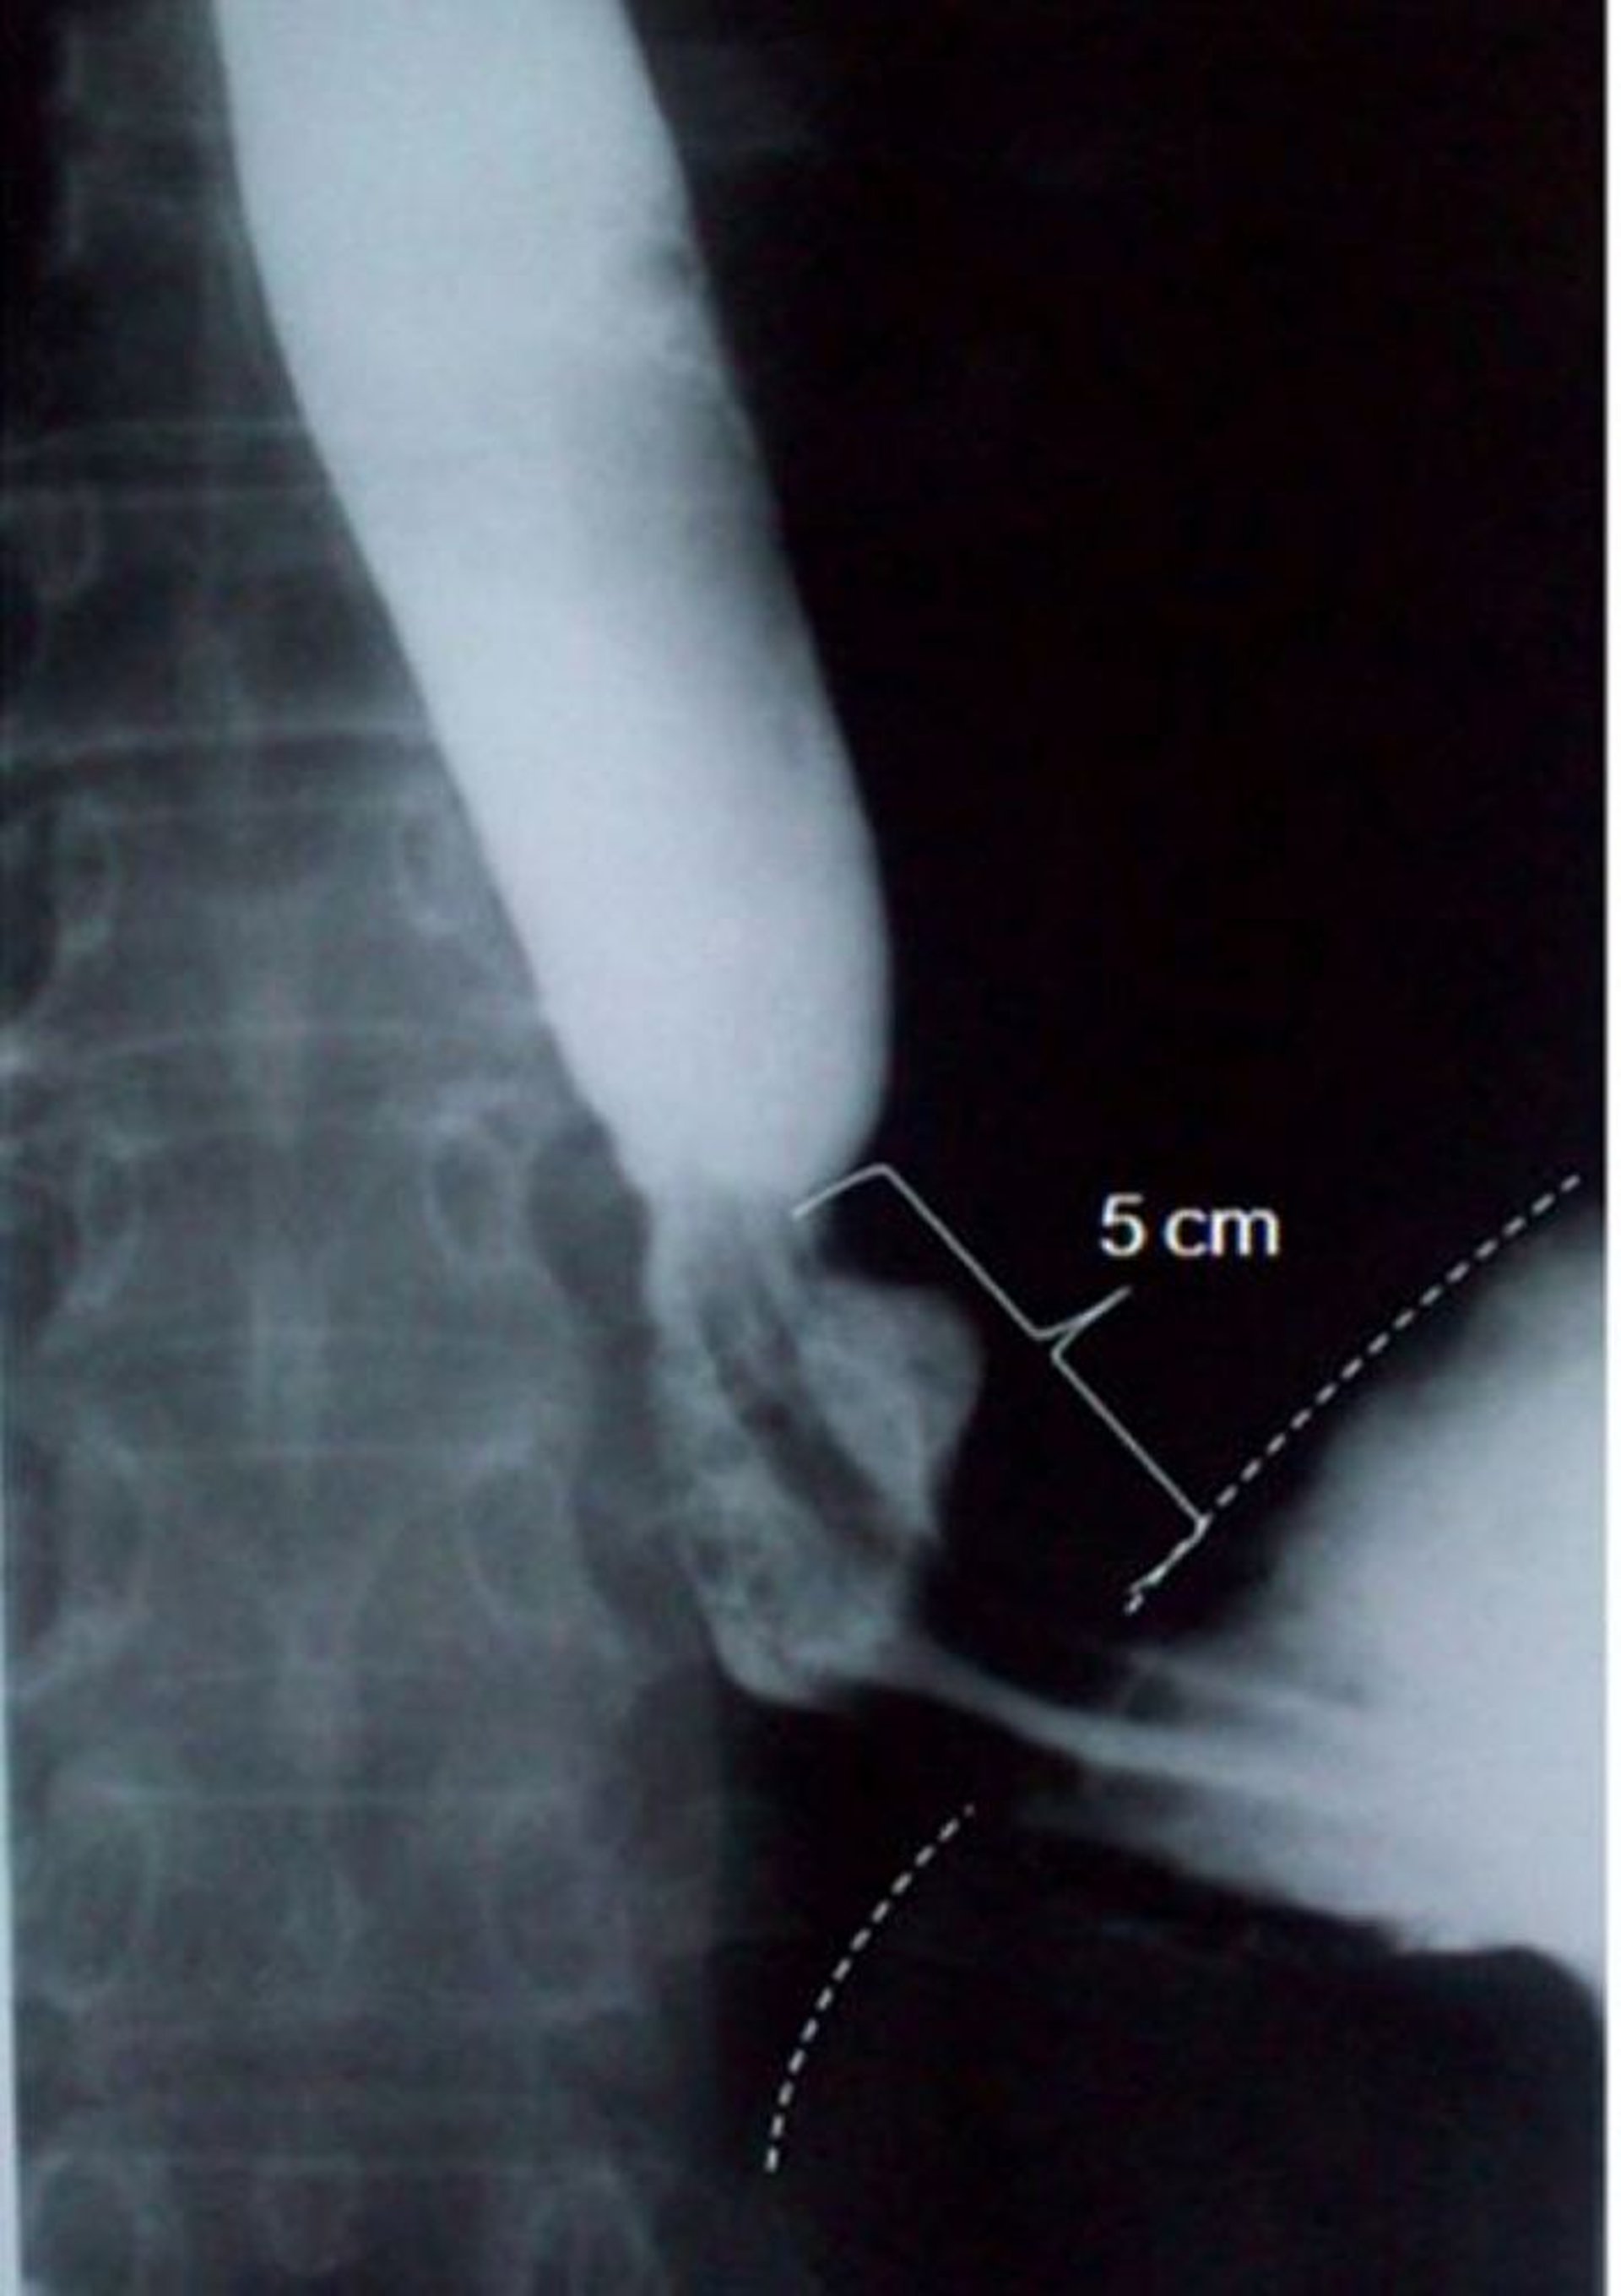

Рентгенографія після проковтування барію демонструє ковзну грижу стравохідного отвору діафрагми

This image shows a sliding hiatus hernia measuring 5 centimeters (5 cm) in axial length (dashed line indicates the diaphragmatic border).